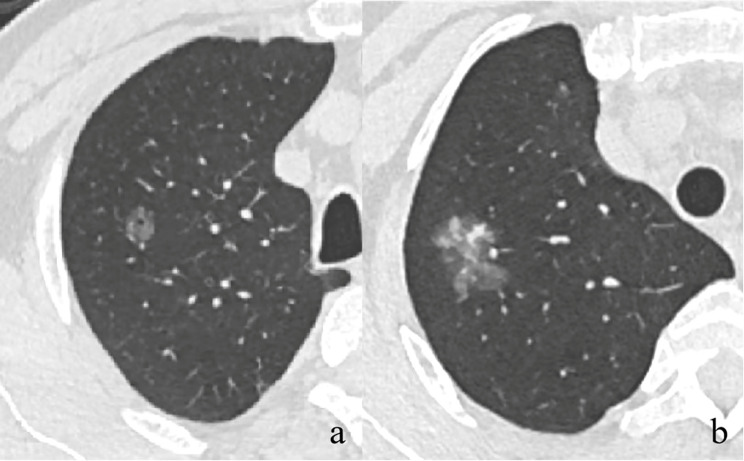

Background: Neoplastic ground glass nodules (GGNs) are relatively indolent tumors, with slow progression in invasiveness and computed tomography (CT) features. This study aimed to explore the correlation between pathological and CT characteristics and gene mutations in neoplastic GGNs.

Methods: We retrospectively analyzed 1,348 neoplastic GGNs from January 2019 to November 2022, including 290 adenocarcinomas in situ (AIS), 448 microinvasive adenocarcinomas (MIA), and 610 invasive adenocarcinomas (IAC). The correlations between patients' characteristics, pathological subtypes and grades, CT features, changes in follow-up, and gene mutations were analyzed.

Results: Solid component (odds ratio [OR] = 1.493; P = 0.014), larger size (OR = 1.049; P = 0.006), ill-defined boundary (OR = 1.368; P = 0.027), and lobulation sign (OR = 1.824; P = 0.001) were revealed as independent CT predictors of gene mutation. From AIS to IAC, the epidermal growth factor receptor (EGFR) mutation rate significantly increased (P < 0.01), while the kirsten rat sarcoma viral oncogene (KRAS) and the anaplastic lymphoma kinase (ALK) mutation rates significantly decreased (P < 0.05). Among IACs, mutation rate was the highest in the intermediate-grade ones (P < 0.05). Gene mutations were more frequently detected in nodules showing changes during follow-up (76.3% vs. 61.1%, P = 0.02), especially in those with more than 2-year follow-up (77.1% vs. 43.7%, P = 0.023). However, the specific changes were not associated with gene mutations (P = 0.273).

Conclusions: Gene mutations in neoplastic GGNs were associated with CT features, pathological subtypes and grades, and changes observed during long-term follow-up.